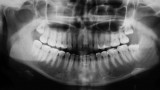

W pierwszym etapie diagnostycznym wykonano zdjęcia zewnątrz- i wewnątrzustne (ryc. 1-12).

Wykonano także modele diagnostyczne zaartykulowane w relacji centralnej (RC), którą zarejestrowano ze względu na zwiększone napięcie mięśniowe z wykorzystaniem deprogramatora Koisa (ryc. 13-15), oraz zdjęcie pantomograficzne (ryc. 16) i cefalometryczne. Analiza modeli w RC wykazała przesunięcie żuchwy w kierunku doprzednim w stosunku do pozycji maksymalnego zaguzkowania i przedwczesne kontakty funkcjonalne na zębach bocznych, co tłumaczyło obecność odprysków szkliwa na brzegach siecznych górnych zębów (szczególnie wyraźne na zębie 12) (ryc. 14, 17). Na modelach wykonano studium funkcjonalne mające na celu określenie, w jaki sposób można odtworzyć prawidłową funkcję, tzn. uzyskać prawidłowy nagryz pionowy i poziomy oraz prowadzenie przednie (ryc. 18-20).